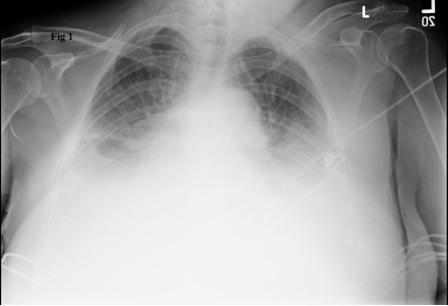

Cardiogenic Shock

Sit the patient up!

High flow O2

DIURESE!

Lasix no max dose (typically 40-120 mg IV )

Nitro patch or spray

Call for help if not improving